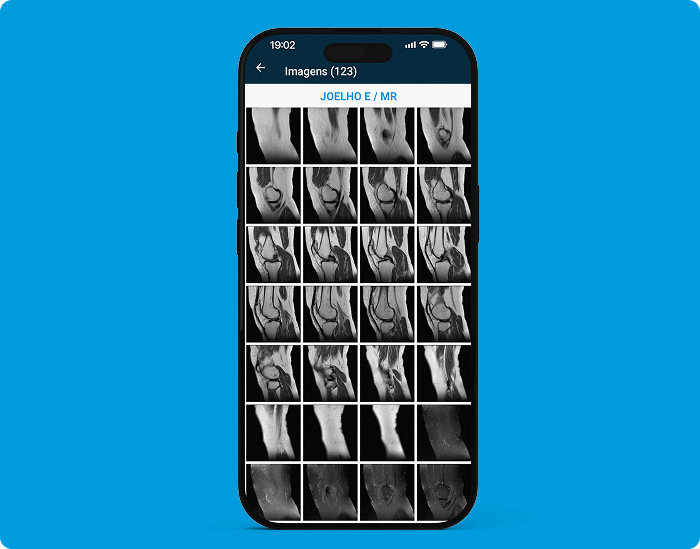

Acceda a imágenes, informes y archivos adjuntos en su teléfono inteligente. Notificar a los pacientes y solicitantes cuando haya un resultado disponible. Inicie sesión a través del CÓDIGO QR para que los pacientes y

solicitantes puedan acceder a los resultados fácilmente.

Acceda a imágenes, informes y archivos adjuntos en su teléfono inteligente. Notificar a los pacientes y solicitantes cuando haya un resultado disponible. Consulte sus resultados desde 1 solo link.